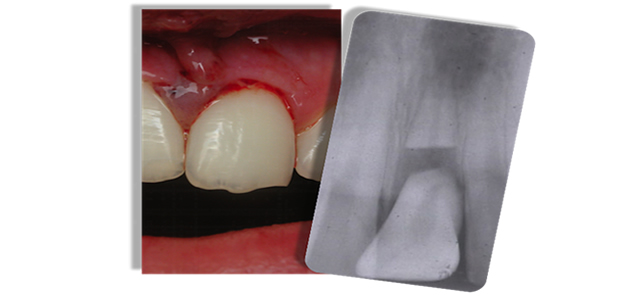

Traumatic Dental Injuries

Traumatic dental injuries often occur in accidents or sports-related injuries. Chipped teeth account for the majority of all dental injuries. Dislodged or knocked-out teeth are examples of less frequent, but more severe injuries. Treatment depends on the type, location and severity of each injury. Any dental injury, even if apparently mild, requires examination by a dentist or an endodontist immediately. Sometimes, neighboring teeth suffer an additional, unnoticed injury that will only be detected by a thorough dental exam. Endodontists are dentists who specialize in treating traumatic dental injuries. With their advanced skills, techniques and technologies they can often save injured teeth.